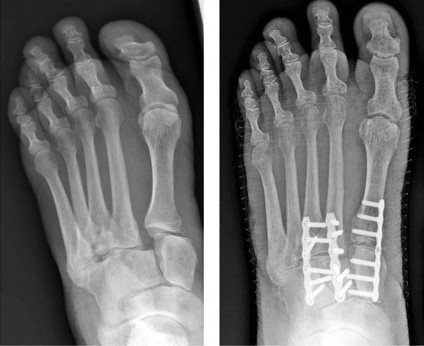

Lisfranc joint injuries are uncommon difficult to diagnose and frequently misdiagnosed. Lisfranc injuries can also result simply from missing the last step on the stairs. A Lisfranc injury occurs when bones break or ligaments tear in the middle region of the feet.

2nd metatarsal is held in mortice created by the three cuneiform bones. Pain swelling and the inability to bear weight are common signs and symptoms. Often mistaken for an ankle sprain a Lisfranc injury is more serious in nature and may take many months to heal.

Lisfranc injuries encompass large spectrum of injuries varying from low energy to high energy complex fracture dislocations. Even a minor slip and fall can cause serious injury. Find Information on Diseases Conditions Sports Injury Personal Injury.

Whilst multiple complex classification systems exist. Five of these long bones the metatarsals extend to the toes. A Lisfranc joint injury is a type of injury to the bones or ligaments or both in the middle part of your foot.

Therefore this study aims to provide a simplified treatment algorithm allowing. Holmgren suffered the injury playing in the annual CrawsOver Pro-Am in Seattle Washington. Ad Find information on chronic and acute pain its causes symptoms and recovery period.